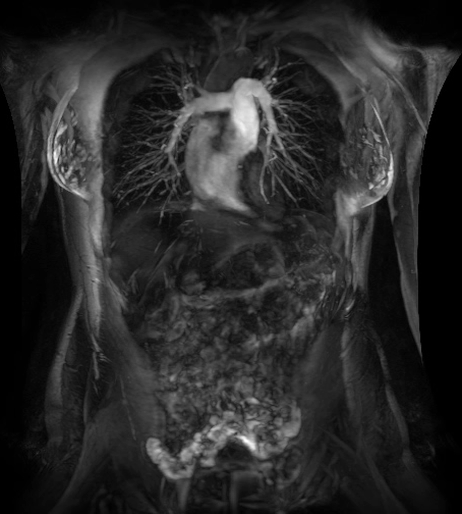

MR,早期肝臟健康(Resoundant)檢查

全面、定量、無(wú)輻射、快速(屏氣)和無(wú)創(chuàng)的肝臟評(píng)估。

定量評(píng)估甘油三酯脂肪濃度和R2 *(IDEAL IQ),肝臟組織硬度即時(shí)分析(MR Touch)??赡苡兄谠u(píng)估非酒精性脂肪性肝病(脂肪)、脂肪性肝炎(炎癥)和肝硬化(纖維化)。致力于讓磁共振成像和活檢一樣精準(zhǔn)、有效。(待FDA 510K審批,未上市銷(xiāo)售)

在乳腺M(fèi)R檢查中,SIGNAWorks?通過(guò)可調(diào)節(jié)線圈元件使得乳腺成像實(shí)現(xiàn)定量化和個(gè)性化,從而實(shí)現(xiàn)精準(zhǔn)醫(yī)療。創(chuàng)新型應(yīng)用——用于超快速動(dòng)態(tài)掃描的DISCO,用于高分辨率形態(tài)成像的Cube T2 with HyperSense和Cube T2 HyperCube,縮短了掃描時(shí)間并促進(jìn)了擴(kuò)散技術(shù)(Focus和MUSE)的發(fā)展,利用與BIRADs一致的CADStream來(lái)探測(cè)組織特征和分析。